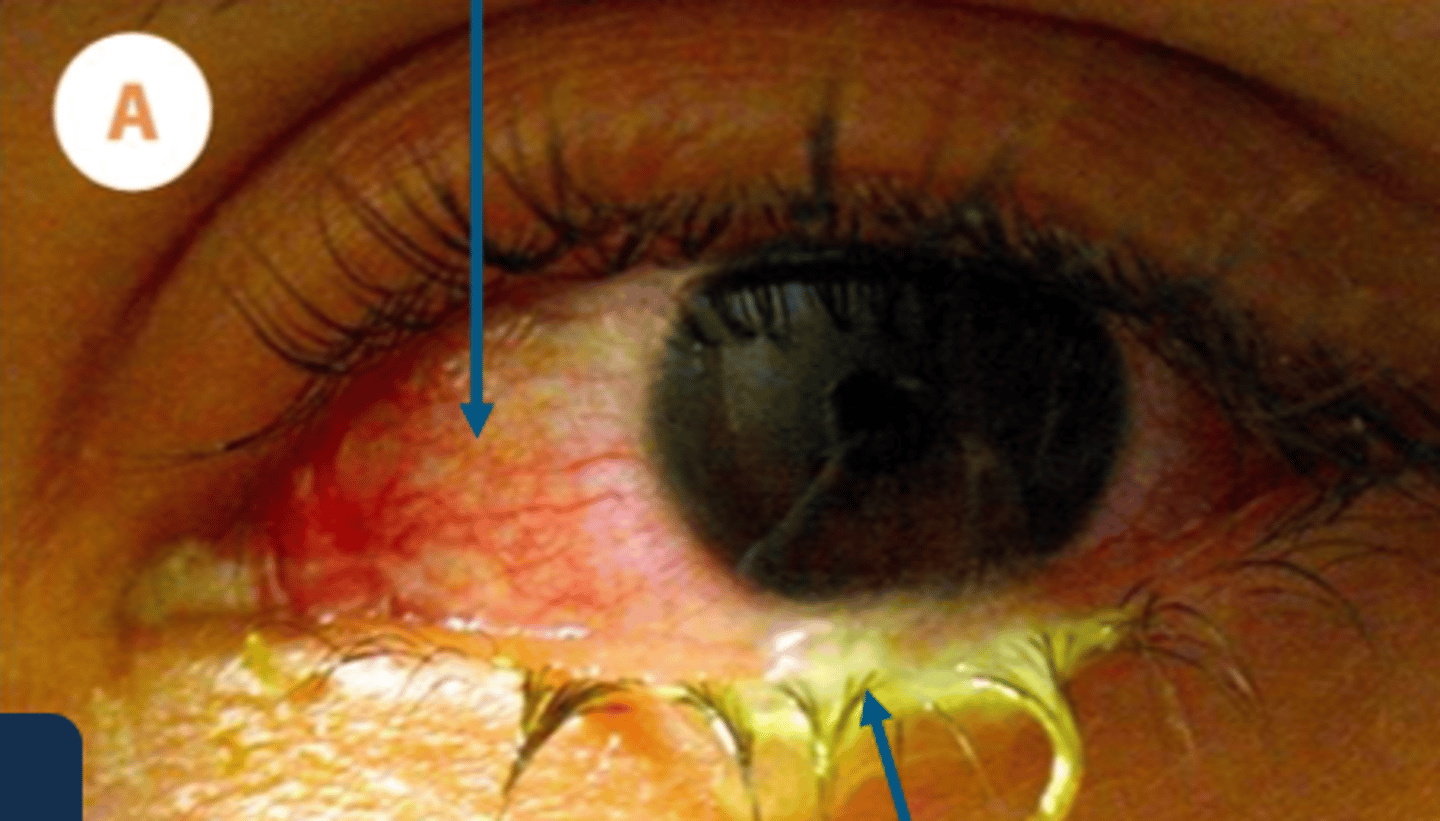

_____ is rapidly progressive severe conjunctivitis characterized by copious purulent discharge and lid edema accompanied by (+) ___ node

in hyperacute conjunctivitis, the presentation is

1. diffuse conjunctival hyperemia & chemosis

2.purulent discharge which is made of pathogen, wbc, dead cells

____ ___ sx include pain, significant white-green discharge, tenderness, blurry vision, photophobia, redness and eyelid crustins

hyperacute conjunctivitis

clinical signs for hyperacute conjunctivitis includes (7)

1. severe purulent discharge

2. + PA node

3. papillae

4. severe lid edema

5. SPK/erosions

6. infiltrates

7. risk for rapid corneal ulceration which lead to perforation